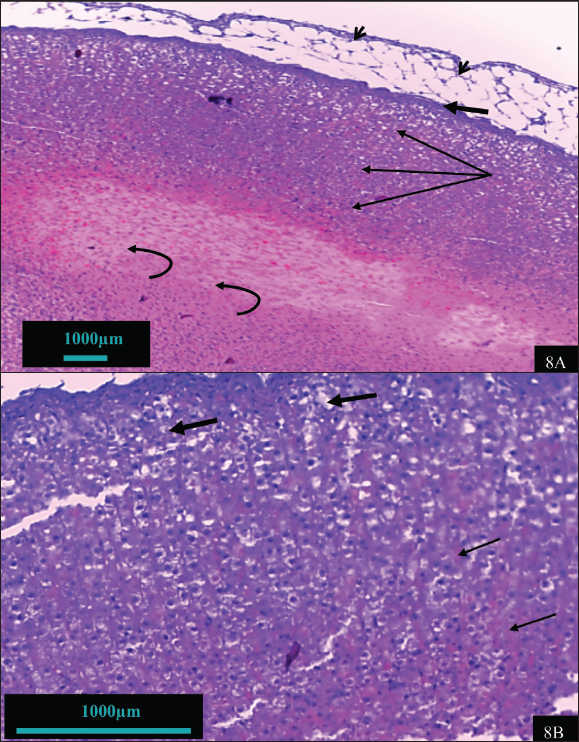

In contrast, the adrenal gland of hypothyroid rats treated with vitamin B12 (hypothyroid + B12) exhibited a notable reparative feature (Fig. 7). Improvements include enhanced capsule integrity, normalization of adrenal cells with clear visible, light-colored nuclei, and restoration of the cellular boundary and cytoplasm. The cell size and number of the cortex and medulla are nearly normal. The features observed in this group are depicted in the control group. The adrenal tissue of rats treated with vitamin B12 exhibited remarkable tissue similarity with the control group (Fig. 8).

Fig. 7. Histomorphohogy of adrenal gland tissues in the hypothyroid rats supplemented with vitamin B12 group showing regular cord-like structures of zona fasciculate (thick arrow), reduced congestion (thin arrow), and slight vacuolations (arrowhead) (7A) (100X). The tissues also showed thick capsule (arrowhead), surrounding adipose tissue (thick arrow), and some nuclei are pale (thin arrow) (7B) (400X). The adrenal cortex showed normal sinusoid (thick arrow) and nucleus (thin arrow) as well as normal cellular architecture (7C); and medulla tissue nearby from normal, chromaffin cell with normal nucleus (thick arrow), as well as slight congestion vascular (arrowhead) (7D).